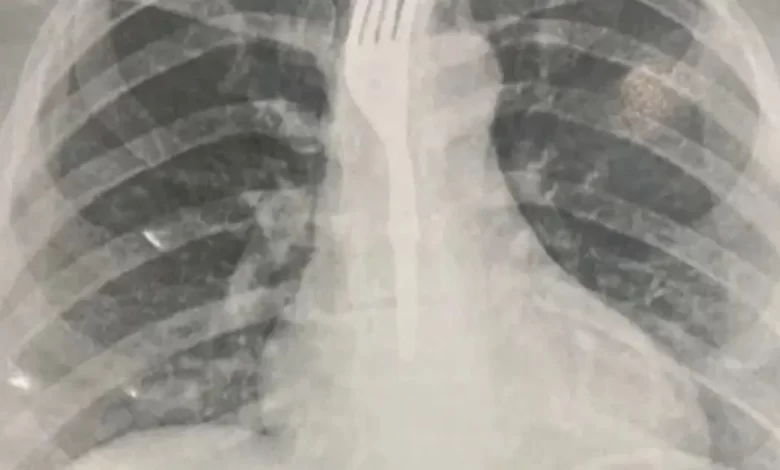

Uma mulher precisou ser transferida para um hospital de Vitória da Conquista, no Sudoeste, após engolir um garfo enquanto fazia uma refeição. Segundo o Achei Sudoeste, o caso ocorreu em Guanambi, no Sertão Produtivo, também Sudoeste do estado.

A mulher, que não teve o nome informado, foi inicialmente levada para o Hospital Geral de Guanambi (HGG), onde exames de imagem apontaram que o objeto estava alojado no esôfago em posição de risco.

Diante da gravidade, os médicos decidiram pela transferência à Vitória da Conquista, onde deve passar por procedimento especializado para retirada do utensílio. O fato ocorreu na última sexta-feira (26) e até esta segunda-feira (29) não há mais informações sobre o estado de saúde da paciente.